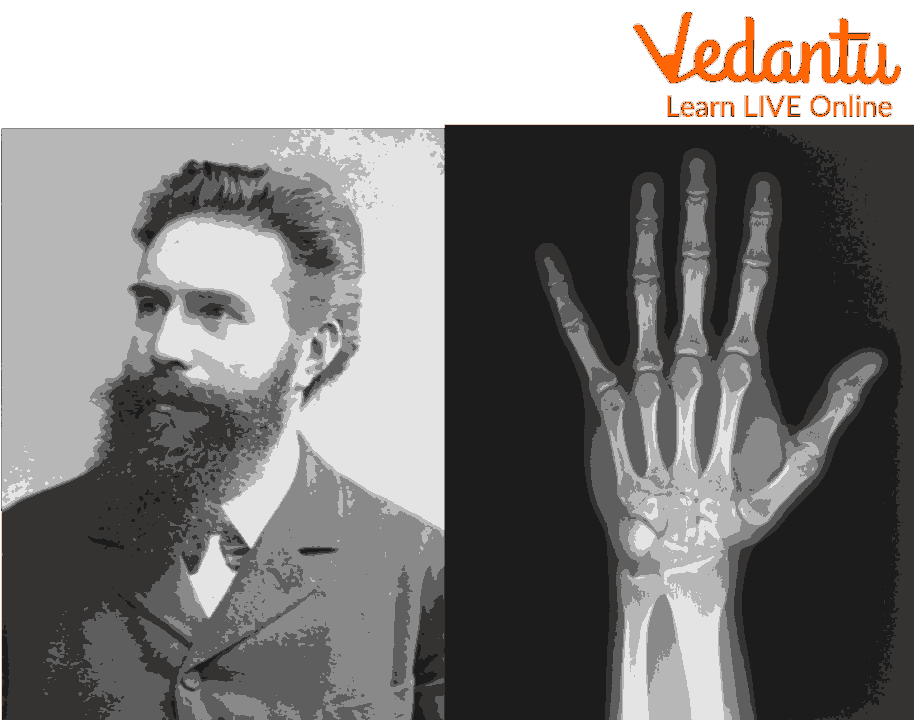

Discovery of X-rays

In 1895, a German physicist Wilhelm Rontgen discovered x-rays accidentally when he was testing whether cathode rays can pass through glass. The cathode tube was covered in heavy paper which was of black colour so he got surprised when he observed that an incandescent green coloured light escaped and projected on a nearby screen. Through experiments he found that the unknown light could pass through most substances and leave shadows of solid objects. He did not know what these rays were, so he named them ‘X’ meaning ‘unknown’ rays.

Wilhelm Rontgen - Physicist Who Discovered X-rays

In 1901, Wilhelm Roentgen's discovery earned him the Physics Nobel Prize.

The innovation of Wilhelm's spouse did not impress Wilhelm's wife. She spoke the words "I have seen my death" after witnessing the picture of her hand.

The invention of the X-ray by Wilhelm, who wanted everyone to profit from its use, resulted in several medical advancements.